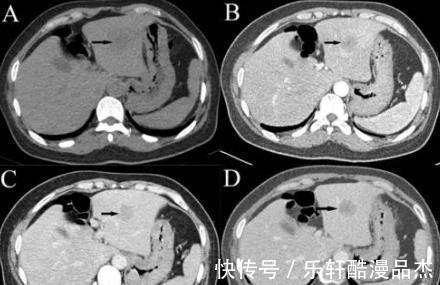

到了医院后,经过检查,刘大哥甲胎蛋白指数已经高达400,严重超标,确诊为肝癌晚期。得知结果的刘大哥一时间愣住了,一时间不知道如何是好,愣过神后刘大哥问医生,我怎么会无缘无故患上肝癌呢?医生了解了刘大哥的饮食情况后,才知道,原来刘大哥日常有经常吃鸭蛋的习惯,几乎每天吃一个,殊不知,经常吃鸭蛋对肝脏的伤害非常大。